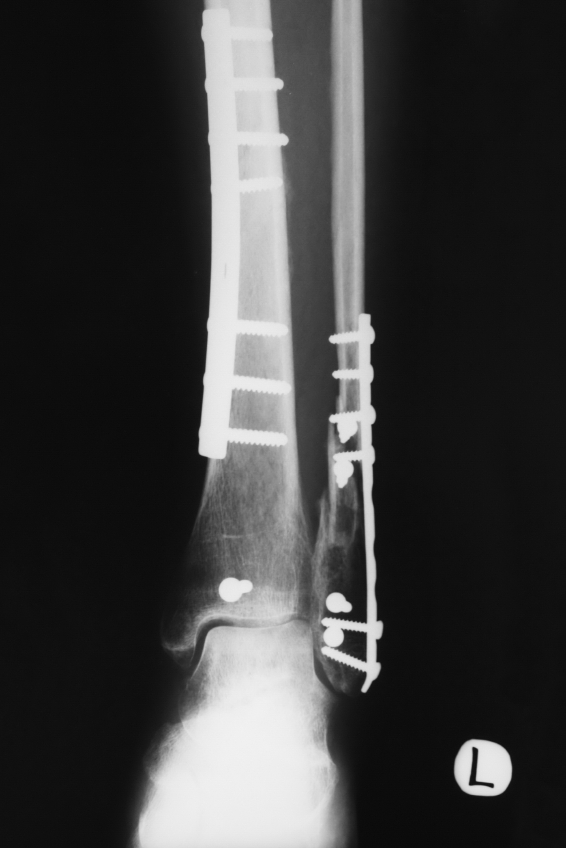

In recent years, doctors have begun performing an Open Reduction Internal Fixation (ORIF) with the goal of having patients start rehabilitation within 3 to 4 weeks. The ORIF procedure involves re-aligning the pieces of the bone and “fixating” them with metal plates and screws. ORIF surgeries require a period of immobility in most cases.

Physicians utilize fixation materials that enable patients to begin moving the involved area or bearing weight on the involved limb in several weeks compared to several months. Within 3 to 4 weeks patients are usually starting a formal rehabilitation program. During rehabilitation, patients are limited in action and activities, but Physical Therapist have the ability to remove the protective splinting/bracing, performing manual techniques and prescribing appropriate exercises that will enhance motion and reduce the swelling and pain in the area. Early controlled motion has proven to reduce the total time of the rehabilitation process.

Weight bearing: For the first several weeks (3-6), patients can expect to use crutches or a walker. The surgeon will take X-rays several weeks after surgery to determine how long a patient must remain non-weight. If the bone shows enough signs of healing, you will be given the ok to become partial weight bearing and the permanent cast will be removed in favor of a removable protective boot. As you progress through the rehabilitation process, you will be given the ok to place more body weight on your involved leg. Based on X-ray studies at future doctor’s visits, you will eventually be told to transition to full weight bearing which usually occurs around the 6-8th week after surgery.